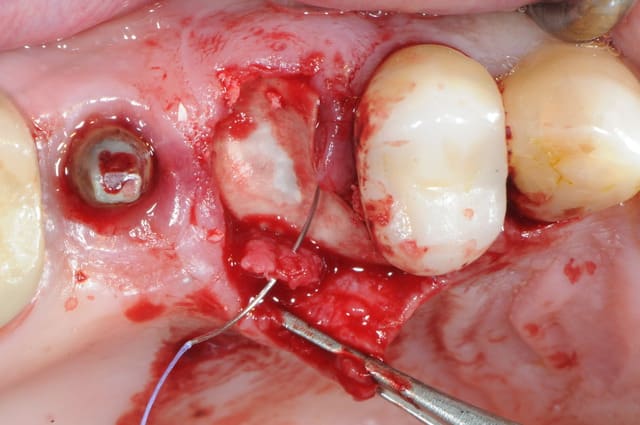

je poursuis donc mon cas clinique si vous voulez bien.

1- curette en appuie sur la face vestibulaire montrant la destruction osseuse.

2- lambeau pleine épaisseur en palatin pour aller chercher un bout de conjonctif qui soit pédiculé.

3 je décole à partit des rebords de la déhiscence osseuse et reste en contacte permanent avec la corticale osseuse tout en décollant la gencive (elle est soulevé donc)

4- comblement avec de la poudre de perlin-pin-pin

( désolé je suis pas au cabinet et je sais plus ce que j'ai mis dedans)

5-6- sutures du conjonctif pour obtenir l'étanchéité (enfin , on essaye)

7- résultat à j+7